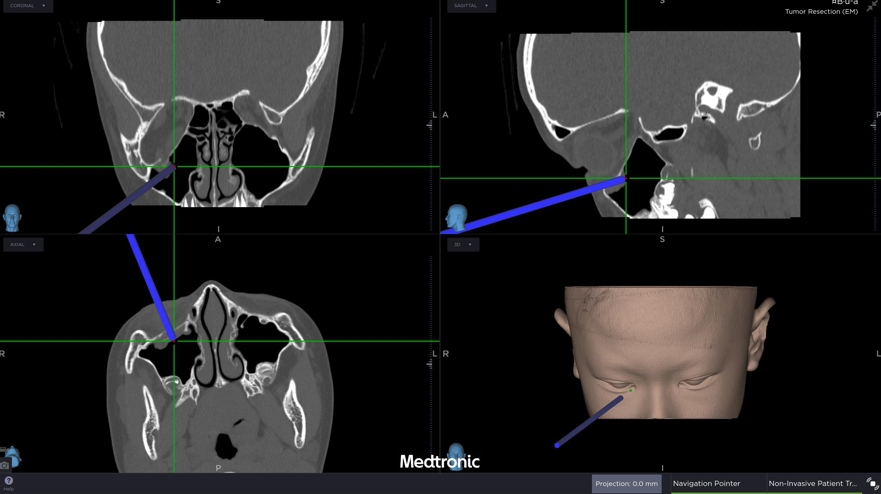

經評估後,中山醫學大學附設醫院口腔顎面外科醫療團隊邱昱瑋主治醫師、張芳語主治醫師及洪珮瑄主治醫師,立即制定手術方案,運用創新電腦數位模擬技術,術中搭配內視鏡與精密導航系統,精準定位眼底嵌頓肌肉的位置,成功將被夾住的眼底肌肉復位。術後,患者複視症狀消失,眼球活動恢復正常,並未留下相關併發症,順利重拾日常生活與學習品質。

中山附醫口腔顎面外科張芳語主治醫師補充,重建受損眼眶骨在臨床上挑戰重重,包括手術視野狹小、骨頭型態複雜、手術精準度要求高,以及術後疤痕與外觀重建的考量,透過精準的數位導航技術,醫師團隊能克服這些困難,幫助患者安全恢復功能與外觀,重拾自信與生活品質。洪珮瑄醫師則強調,對於兒童患者而言,手術精準度與微創性格外重要,不僅要恢復功能,更要兼顧未來面容發育的完整性;該起案例不僅展現數位導航手術在顏面骨折治療上的價值,也提醒家長與學校,即便外觀無傷痕,一旦出現眼球運動受限或複視症狀,應立即就醫,避免錯過黃金治療期。